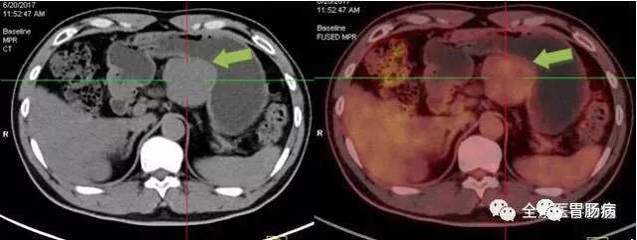

3、爸爸得了胃部恶性间质瘤,但切除下来的瘤里面有坏死现象,这样是不是好…

这个病一定要坚持锻炼,但是一定不能累。有计划的运动有助于恢复体能,提高抵抗力。胃肠道间质瘤目前有特效药,格列卫。你可以用它。坏死和有丝分裂都是恶性的证据。肿瘤坏死是某些食物和药物中肿瘤坏死因子的结果。如果自身免疫系统的免疫细胞能及时清理这些坏死组织,肿瘤就会消散。这是一个好现象。不要急着干重体力活。建议按照以下饮食计划来管理自己的饮食。